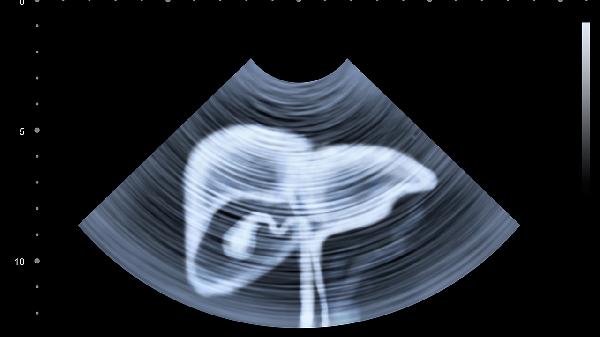

水果摊前挑挑拣拣时,你是否也常把"只是坏了一小块"的水果带回家?一位50岁大叔的遭遇或许能给你敲响警.钟——连续半年食用轻微腐烂的水果后,他因食欲骤减就医,最终确诊肝癌。妻子在诊室外崩溃:"都怪那些发霉的水果..."这绝不是危言耸听,那些你舍不得扔的"小霉点",可能正在悄悄摧毁你的肝脏。